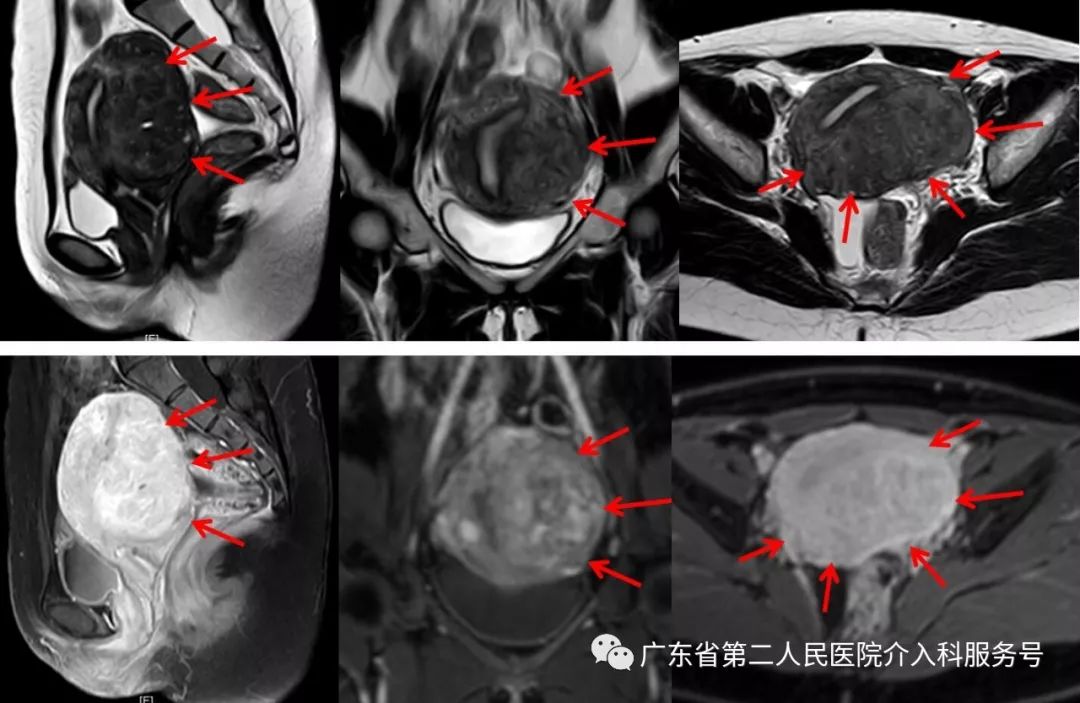

广东省第二人民医院介入科磁共振检查:子宫明显增大(11.6*9.5*8.1cm3),子宫腺肌症,以后壁、左侧壁及宫底明显(如下图)。